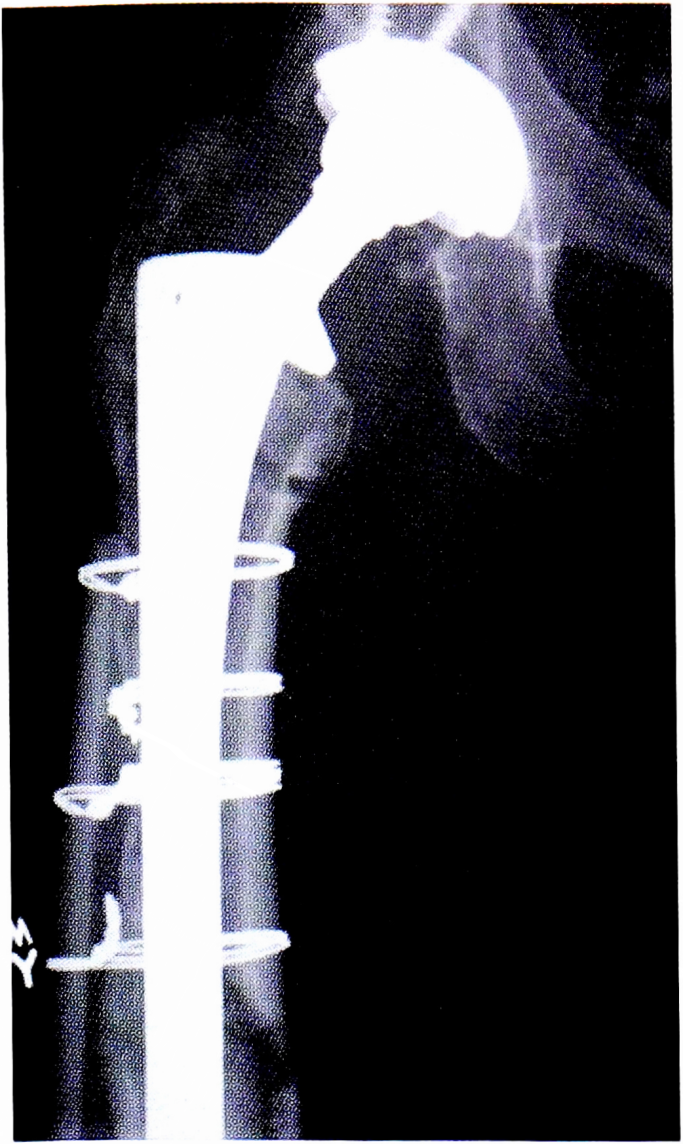

Перфорации типа С1 (область дистального метафиза) требуется импактировать костными аллотрансплантатами. Лечение переломов типа С2 (стабильные, в области дистального метафиза) включает фиксацию серкляжной проволокой и кортикальными аллотрансплантатами, выполняющими аугментирующую роль (рис. 7). Самыми сложными в плане лечения являются интраоперационные переломы типа С3 (нестабильные, в области дистального метафиза (рис. 8), которые чаще всего возникают при вывихивании БК. Их лечение заключается в открытой репозиции отломков и металлоостеосинтезе [27, 34, 36].

Fig. 8. Intraoperative periprosthetic fracture C3. Fixation by cerclage wire and metal osteosynthesis.

Рис. 8. Интраоперационный перипротезный перелом типа С3. Фиксация серкляжной проволокой и металлоостеосинтез пластиной (https://www.orthobullets.com/recon/5013/thaperiprosthetic-fracture).